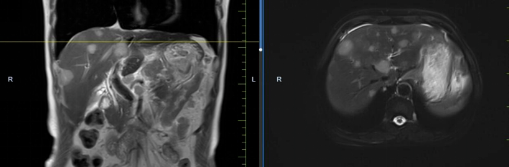

患者馬某某,男,60歲,因腹部不適行胃鏡及腹部CT,提示胃癌、多發(fā)淋巴結(jié)轉(zhuǎn)移、肝轉(zhuǎn)移,胃部病灶大小約11*6cm,淋巴結(jié)最大病灶約6*3cm,肝臟病灶最大約8.8*7cm。經(jīng)6周期化療+免疫,聯(lián)合中醫(yī)中藥后,病灶明顯縮小,進(jìn)入維持治療階段,身體狀況與常人無異。

治療前

治療后